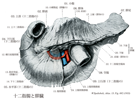

十二指腸【じゅうにしちょう】 The ca. 25-30 cm long segment of the small intestine between the pylorus and duodenojejunal flexure.(十二指腸は胃の幽門から十二指腸空腸曲まで約25cmの腸管。十二指腸Duodenumは12で、intestinum duodenum digitorumの意味。長さが指を12本横にならべた幅に等しいことによる。第1腰椎の椎体右縁の前方ではじまり、C字状に屈曲して膵臓の頭を取り囲む。腸間膜を欠き、後腹膜臓器の一つであり、胆管、膵管が開口するなど他の小腸とは異なる。十二指腸には4部が区別される。上部は幽門につづく5cmの長さの部で、上背外側へはしる。最初の2.5cmは可動性。上縁には小綱が付着する。上十二指腸曲において、ほぼ下方へ屈曲し、下行部(約8cm)へ移行する。その半ばで後内側壁に一条の十二指腸ヒダがり、その下端に大十二指腸乳頭が隆起し、ここに総胆管と膵管が共通に開口する。その上方2~3cmの部に小十二指腸乳頭があることが多く、副膵管の開口をみる。下行部は下十二指腸曲で左方へ屈曲し、水平部(下部、約8cm)へ移行し、第3腰椎体左縁に達し、左上方へ屈曲し、上行部へつづく。この部は約5cm走行したのち、第2腰椎の左方で急に前方に曲がり空腸へ移行する。この部を十二指腸空腸曲という。この曲がりは、横隔膜直下の後大動脈壁から下降する十二指腸提筋で固定されている。十二指腸の前半、ほぼ大小十二指腸乳頭までには、よく発達した十二指腸腺がある。複合管状胞状腺で、分泌物は粘液性でアルカリ性を示すことから胃酸から粘膜を保護するのではないかといわれる。)